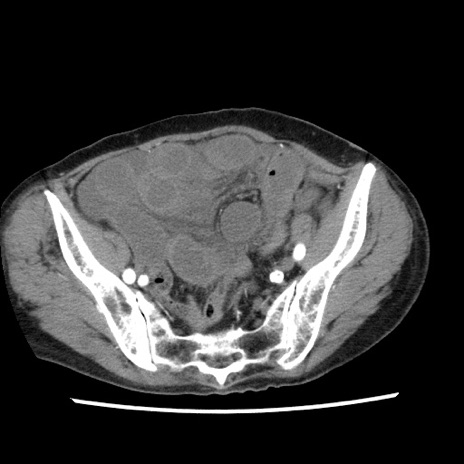

冠状断像

【症例】80歳代女性

【主訴】腹痛

【現病歴】8時間前から腹痛あり来院。

【既往歴】糖尿病、脂質異常症、子宮体癌にて子宮全摘術

【身体所見】意識清明・会話良好だが腹痛で苦悶様、全腹部にわたって反跳痛と圧痛あり

【データ】WBC 13600、CRP 0.14、LDH 224、CK 90